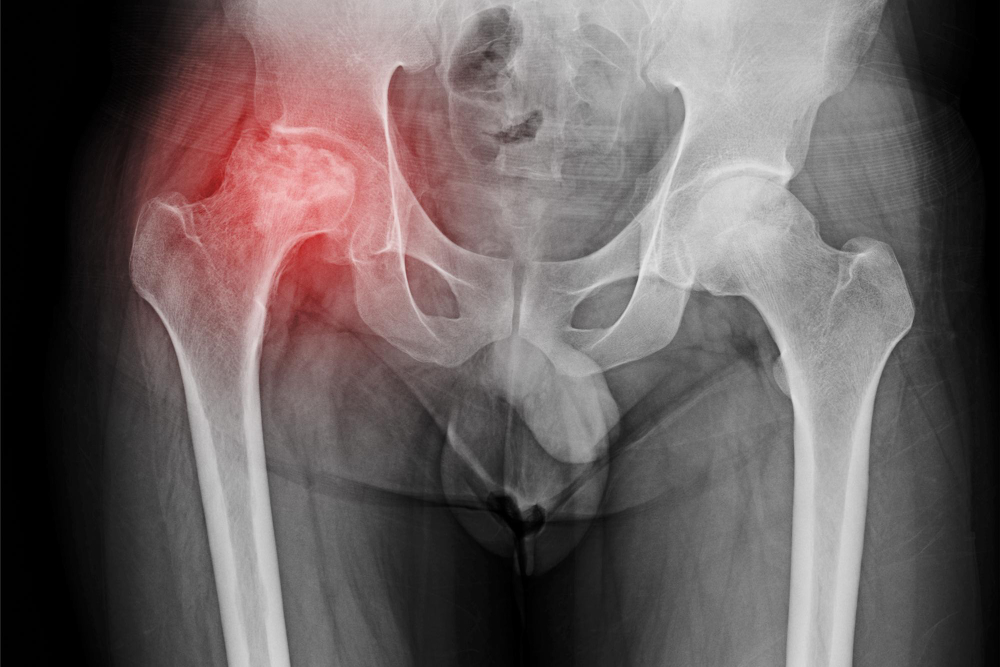

Diagnosis

Doctors use several steps to diagnose avascular necrosis of hip. First, they ask about your symptoms and medical history. Next, they perform a physical exam. If they suspect hip bone death, they may order tests such as:

Early diagnosis is key. With quick action, you can prevent more damage to the hip joint.